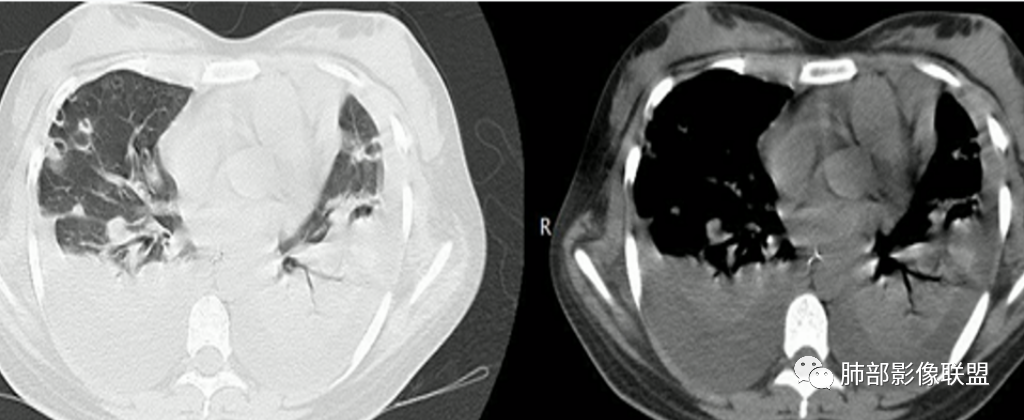

同样是血播的,金葡与肺克比较,金葡更趋于磨玻璃,肺克更趋于实变。给肝脏层面,作者的意思,就是告诉你没有肝脓肿。

青少年,高处跳落游泳史,左侧盆部疼痛(怀疑皮肤损伤),畏寒发热,CRP和Pct显著升高,感染性休克表现(提示革兰阴性杆菌),双肺叶外周分布为主棉絮状结节及斑片影,GGO密度,边缘清,间质及实质改变,病灶内细网格影,见供血血管证,分布特点双肺叶Spe表现,考虑大肠杆菌导致血行感染,血培养检查!

青少年男性,2天游泳后发热,双肺多发斑片状,结节状阴影,多分布肺外带,血道来源,部分病灶边缘可见磨玻璃影,患者有明显脂肪肝病史,考虑.感染性病变,金黄色葡萄球菌?钩体?肺克?

双肺叶结节及斑片状磨玻璃样密度,边缘清,外周分布为主,部分见供血血管,分布特点符合Spe表现,青少年,高处跳落游泳史,左侧盆部疼痛,畏寒发热,CRP和Pct显著升高,考虑血行感染,金葡?至于大家考虑的钩端螺旋体病和嗜水单胞菌不是太了解

2.影像上肺多发混合密度片影,随机分布,胸膜下分布优势,病灶边界大多隐约可辨,偏柔和,动脉血管影穿行,未见钙化、液化空洞、或明确气囊影,未见树芽征。

3.双侧胸腔未见积液。双肺门及纵隔未见增大淋巴结。

4.肝左右叶密度减低,未见结节影、块影或液化区。

3.影像方面:双肺多发病灶,随机分布,且有相当部分沿胸膜下,是可以符合血流感染的。